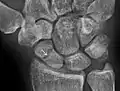

التشخيص

يتم عادة تشخيص كسر العظمة الزورقية بالتصوير بالأشعة السينية الجانبية, ولكن لا تظهر جميع الكسور في البداية ولذلك الناس اللذين يعانون من الم عند الضغط على منطقة السعوط يضعون جبيرة عصابة الإبهام من سبع إلى عشر أيام وحينها يتم اخذ مجموعة أخرى من صور الأشعة السينية.

وإذا كان هناك كسر شعري سيكون الشفاء واضحا, وحتى في ذلك الحين لن يكون كسر العظمة الزورقية واضحا, ويتم اخذ صورة بالأشعة المقطعية لتقيم العظمة الزورقية بوضوح أكبر, كما انه يفضل التصور بالرنين المغناطيسي إذا توفر عن التصوير بالأشعة المقطعية لأنه يمكن ان يعطي تشخيصا فوري. ويعد لا يظهر التصوير الملون طريقة فعالة لتشخيص الكسر الذي في صور الأشعة السينية.

معرض صور